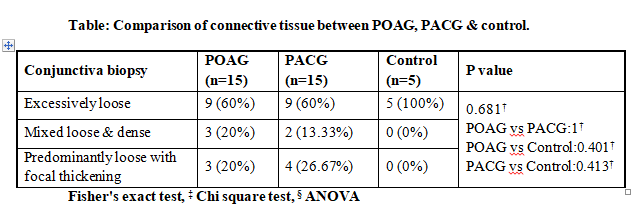

Connective tissue studied in conjunctival biopsy specimen was divided into 3 main types- excessively loose, mixed loose & dense and predominantly loose with focal thickening.

The comparison of POAG & PACG group respectively with control group as well as with each other was not statistically significant.